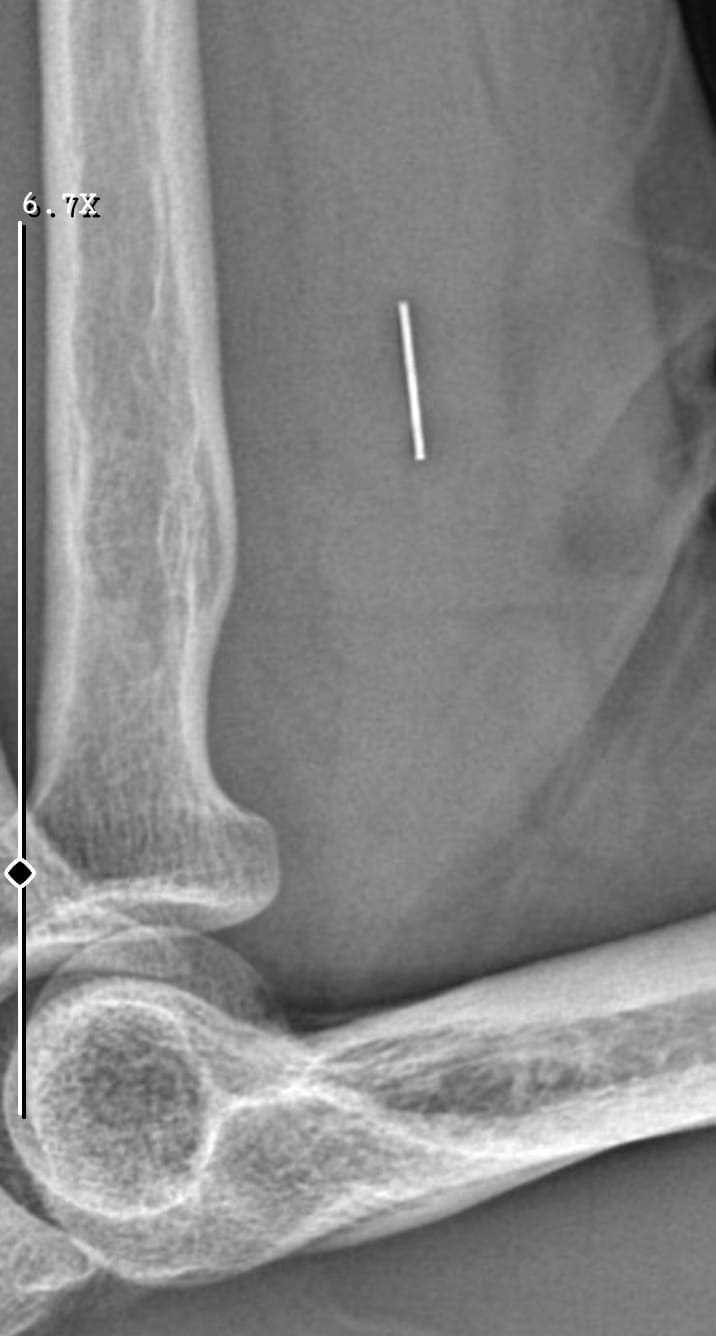

Öte yandan, ameliyatların ardından ağrıları devam eden Güleryüz’ün kolunda metal parça bulunduğu ve bu parçanın parmak bölgesinden dirseğe doğru ilerlediği öne sürüldü. Ayrıca, fabrikada temizlik personeli olarak çalışan Nurettin Güleryüz’ün hastane sürecinde işten çıkarıldığı da öğrenildi.

"Doktorlara bileğime doğru ağrılarım olduğunu sürekli ifade etmeme rağmen beni dinlemediler. Sonradan kolumda metal kaldığını öğrendik. Bunun ihmal olduğunu düşünüyoruz. Çünkü kola metal nasıl girebilir? Ben 9 aydır çalışamıyorum. Kalp rahatsızlığım sebebiyle yüzde 46 engelliyken şu anda yüzde 75 engelli durumuna düştüm. Erken emeklilik dilekçesi verdim ancak henüz sonuç gelmedi. Bu konuda çok mağdurum. Yetkililerin bunu duymasını istiyorum. Savcılığa suç duyurusunda bulunduk. Yaklaşık 9 aydır henüz soruşturma izni gelmedi. Süreci bekliyoruz, henüz dava açılmış değil. Kolumda bırakılan metal ilerliyor. Pazartesi günü bunun için de operasyon geçireceğim. Çıkarılıp çıkarılamayacağı net değil. Elimde titremelerim var, çalışamıyorum ve işveren tarafından işten çıkarıldım. Yetkililerden destek ve konunun incelenmesini talep ediyorum."